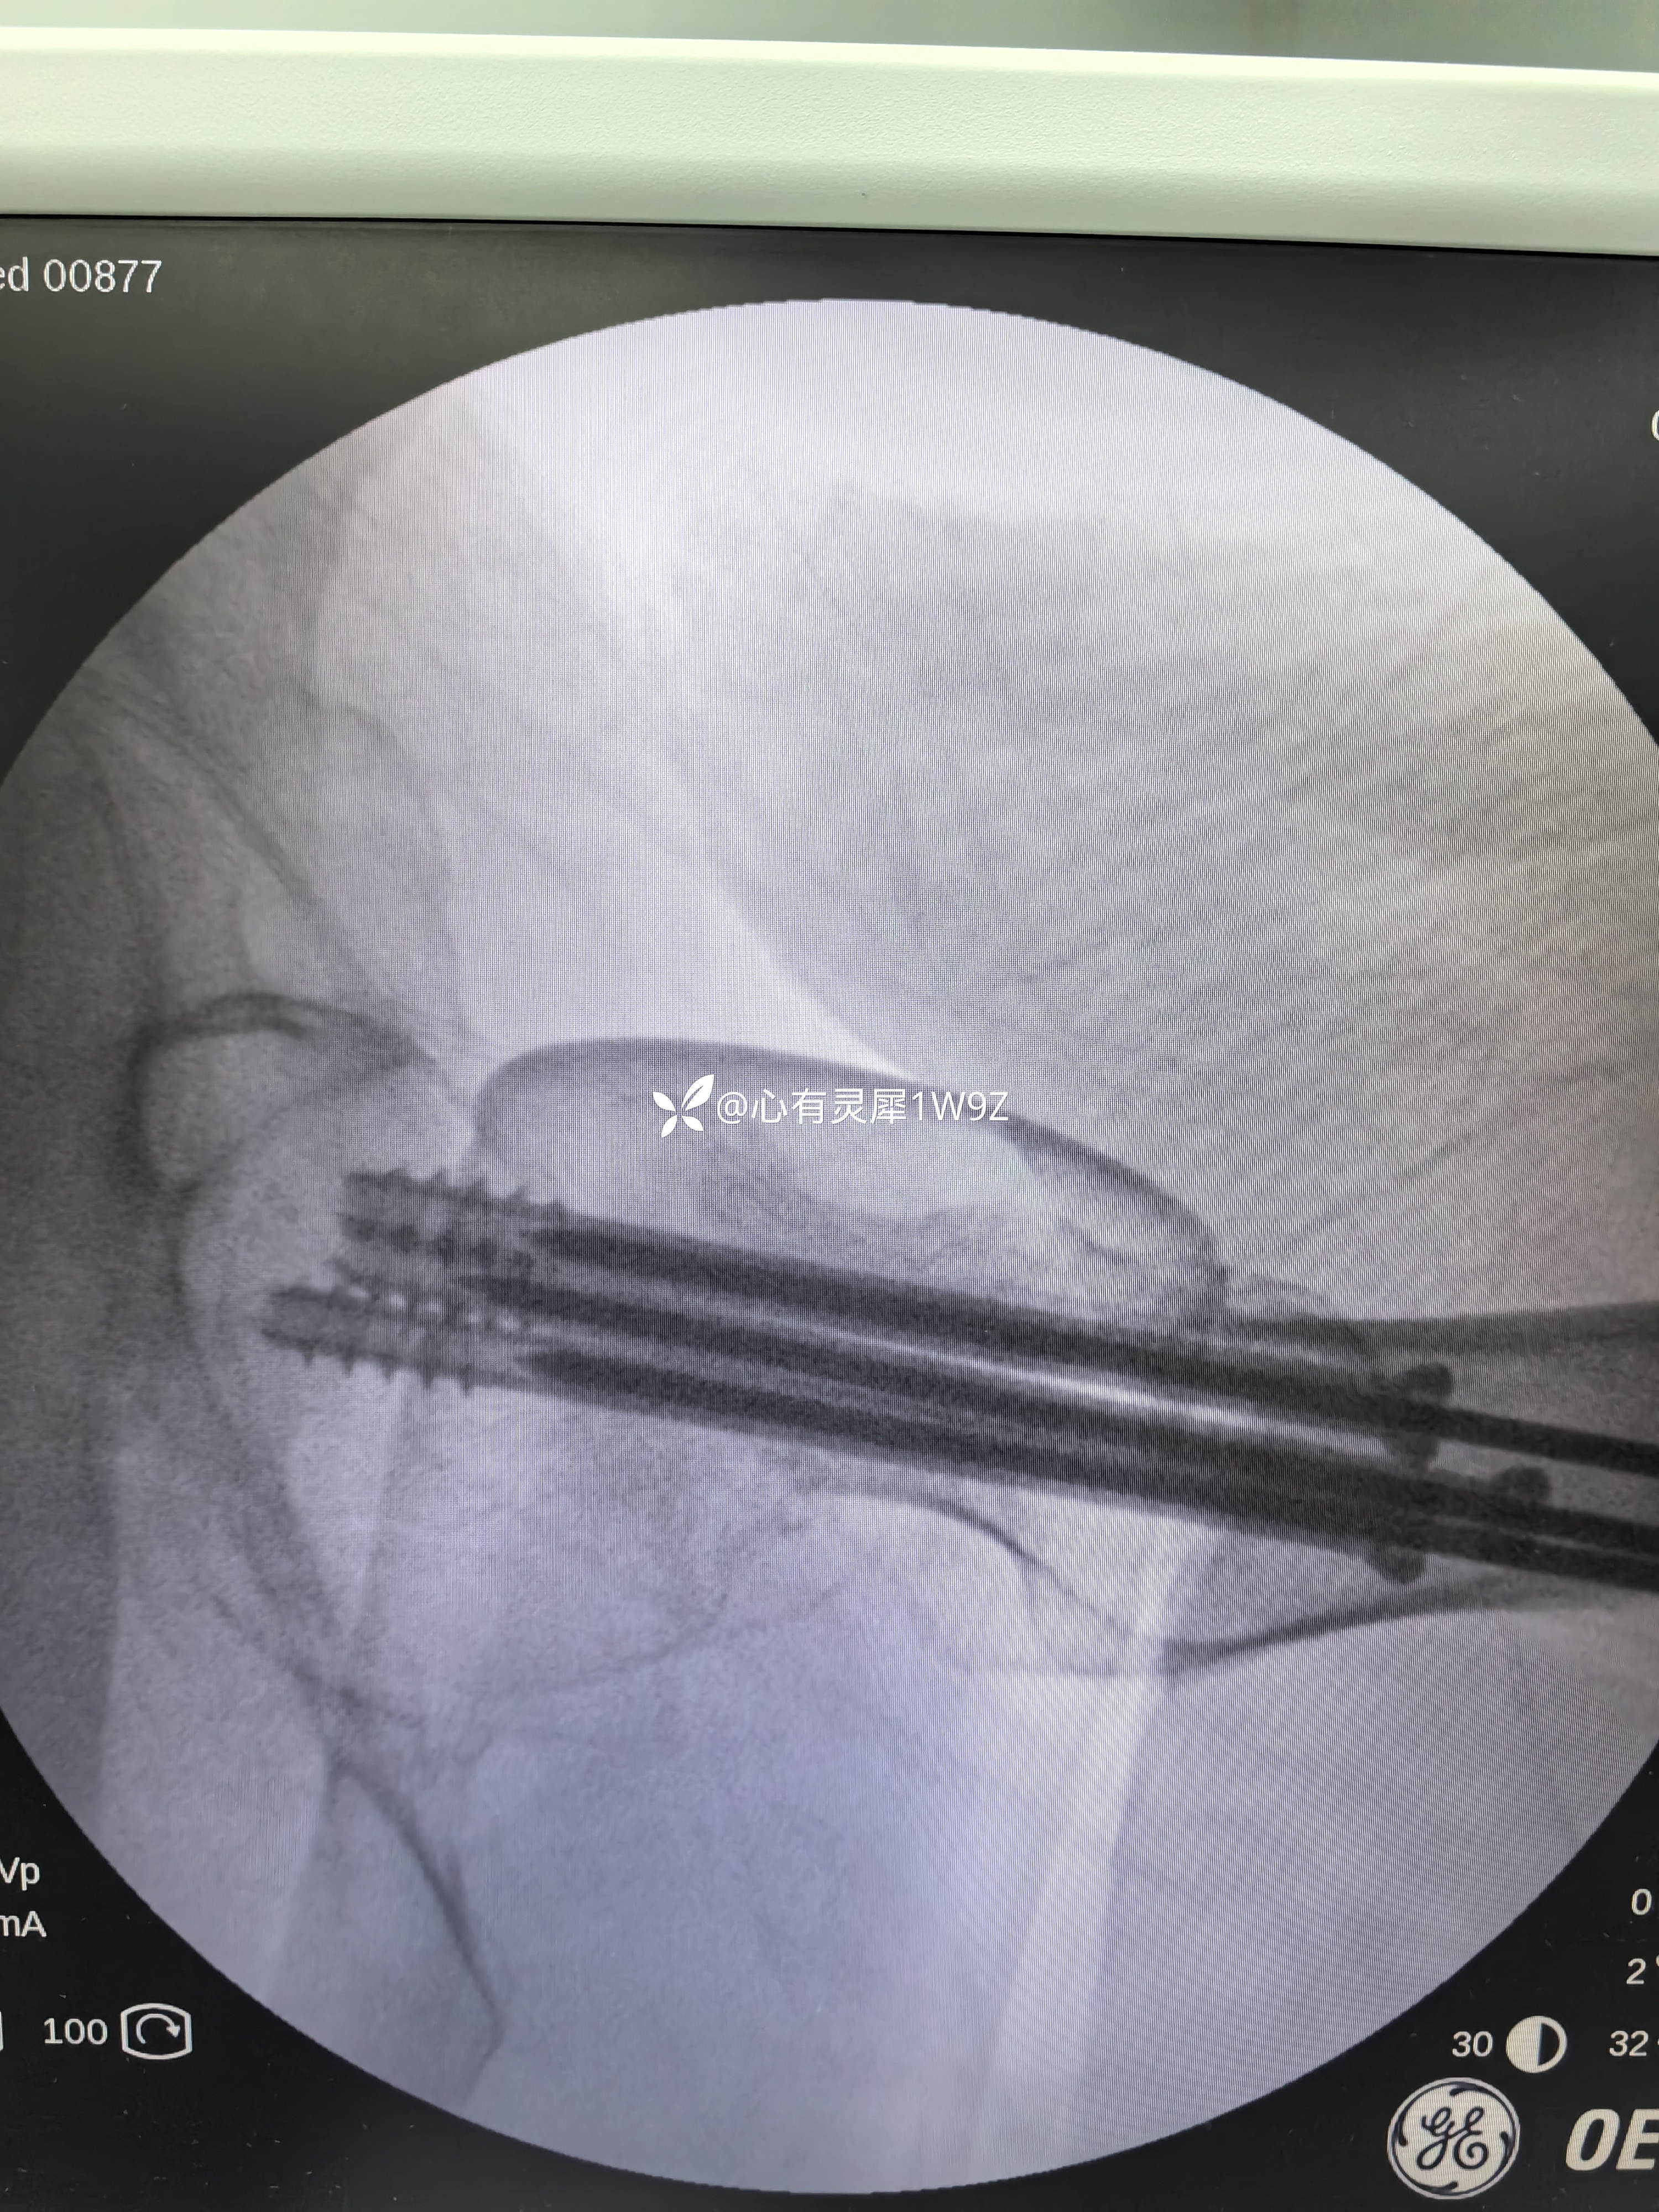

向患者及家属讲解治疗方案。患者和家属选择做内固定。积极准备后在24小时内手术。椎管麻醉,手术顺利,计划首先闭合复位,复位失败就切开复位,三枚加压空心钉固定。

2,关于贴壁,平行,长度,角度。自己感觉这次平行和长度都比较满意,贴壁还可以,角度不是很完美,感觉可以接受,就没有再调整。